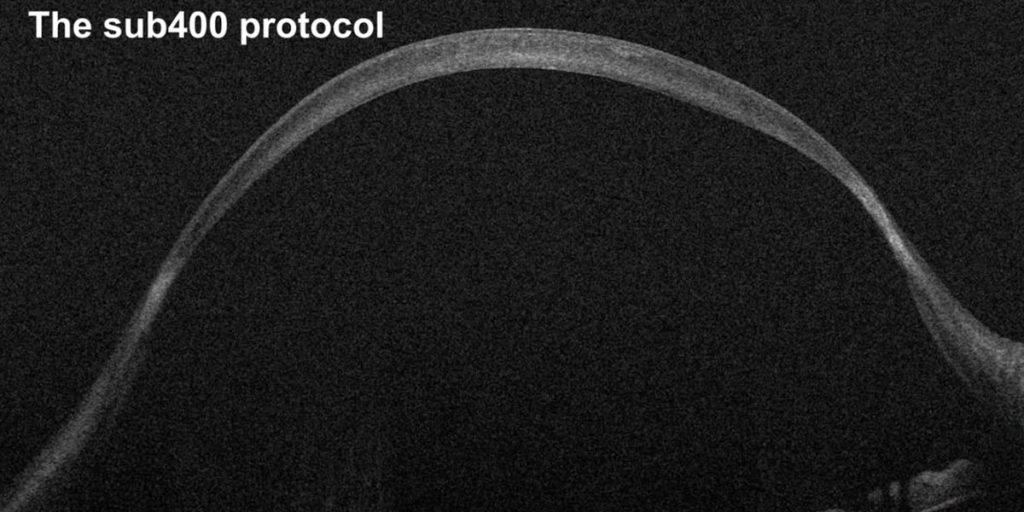

The ELZA Institute’s Prof. Hafezi has revealed the “sub400” cross-linking protocol for thin corneas with keratoconus. Until now, these corneas had to be swollen with hypoosmolar riboflavin or have a collagen contact lens added to make the cornea thick enough to be cross-linked. No longer. sub400 makes the procedure safer, simpler, with no requirement for these thickness “hacks”. The ELZA Institute have successfully used sub400 to cross-link corneas as thin as 220 µm – watch the video to find out more!